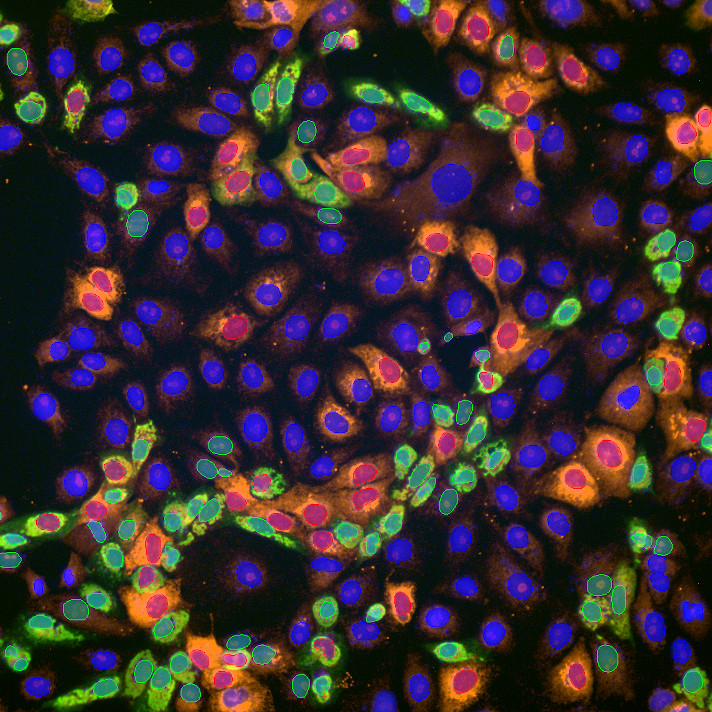

2 Detection and segmentation

3 Feature Extraction

4 Adaptive Classification

- Cell and object detection/segmentation – Identifying and segmenting structures within images.

- Feature extraction – Analyzing image data to extract relevant features.

BIAS supports both classical segmentation methods (f.x. auto-thresholding) and modern deep-learning-based models based cellular or subcellular structure segmentation models.

- Our generic models can handle a wide range of imaging modalities.

- We also offer specialized models tailored for specific tasks.

For phenotype classification, BIAS provides an interactively trainable system that supports both feature-based and image-based algorithms. Users can customize classification models to fit the specific needs of their project.